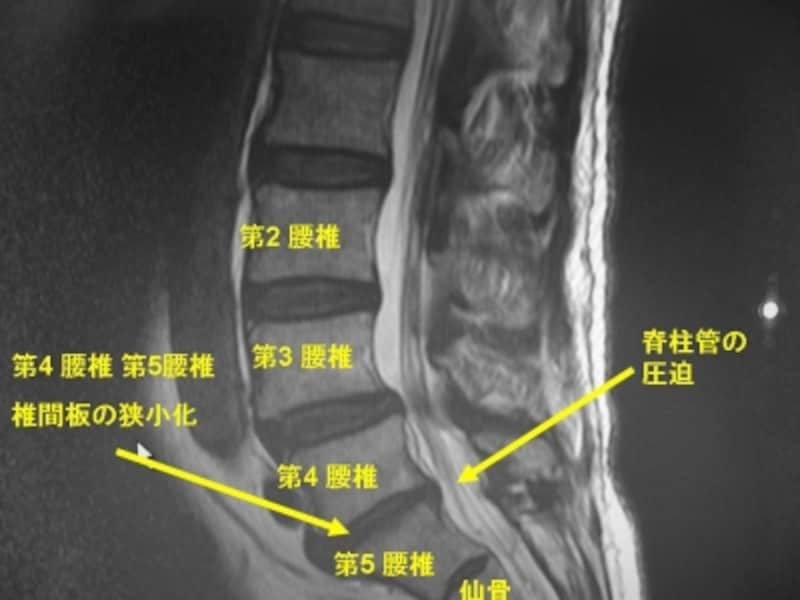

■MRI

MRIは専用の病院で撮影を行いました。

MRI写真 腰部脊椎が前方から強く圧迫されています 椎間板が狭くなっていることもレントゲンより鮮明にわかります